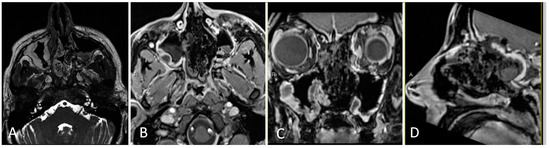

3.4.2. Illustrative Case